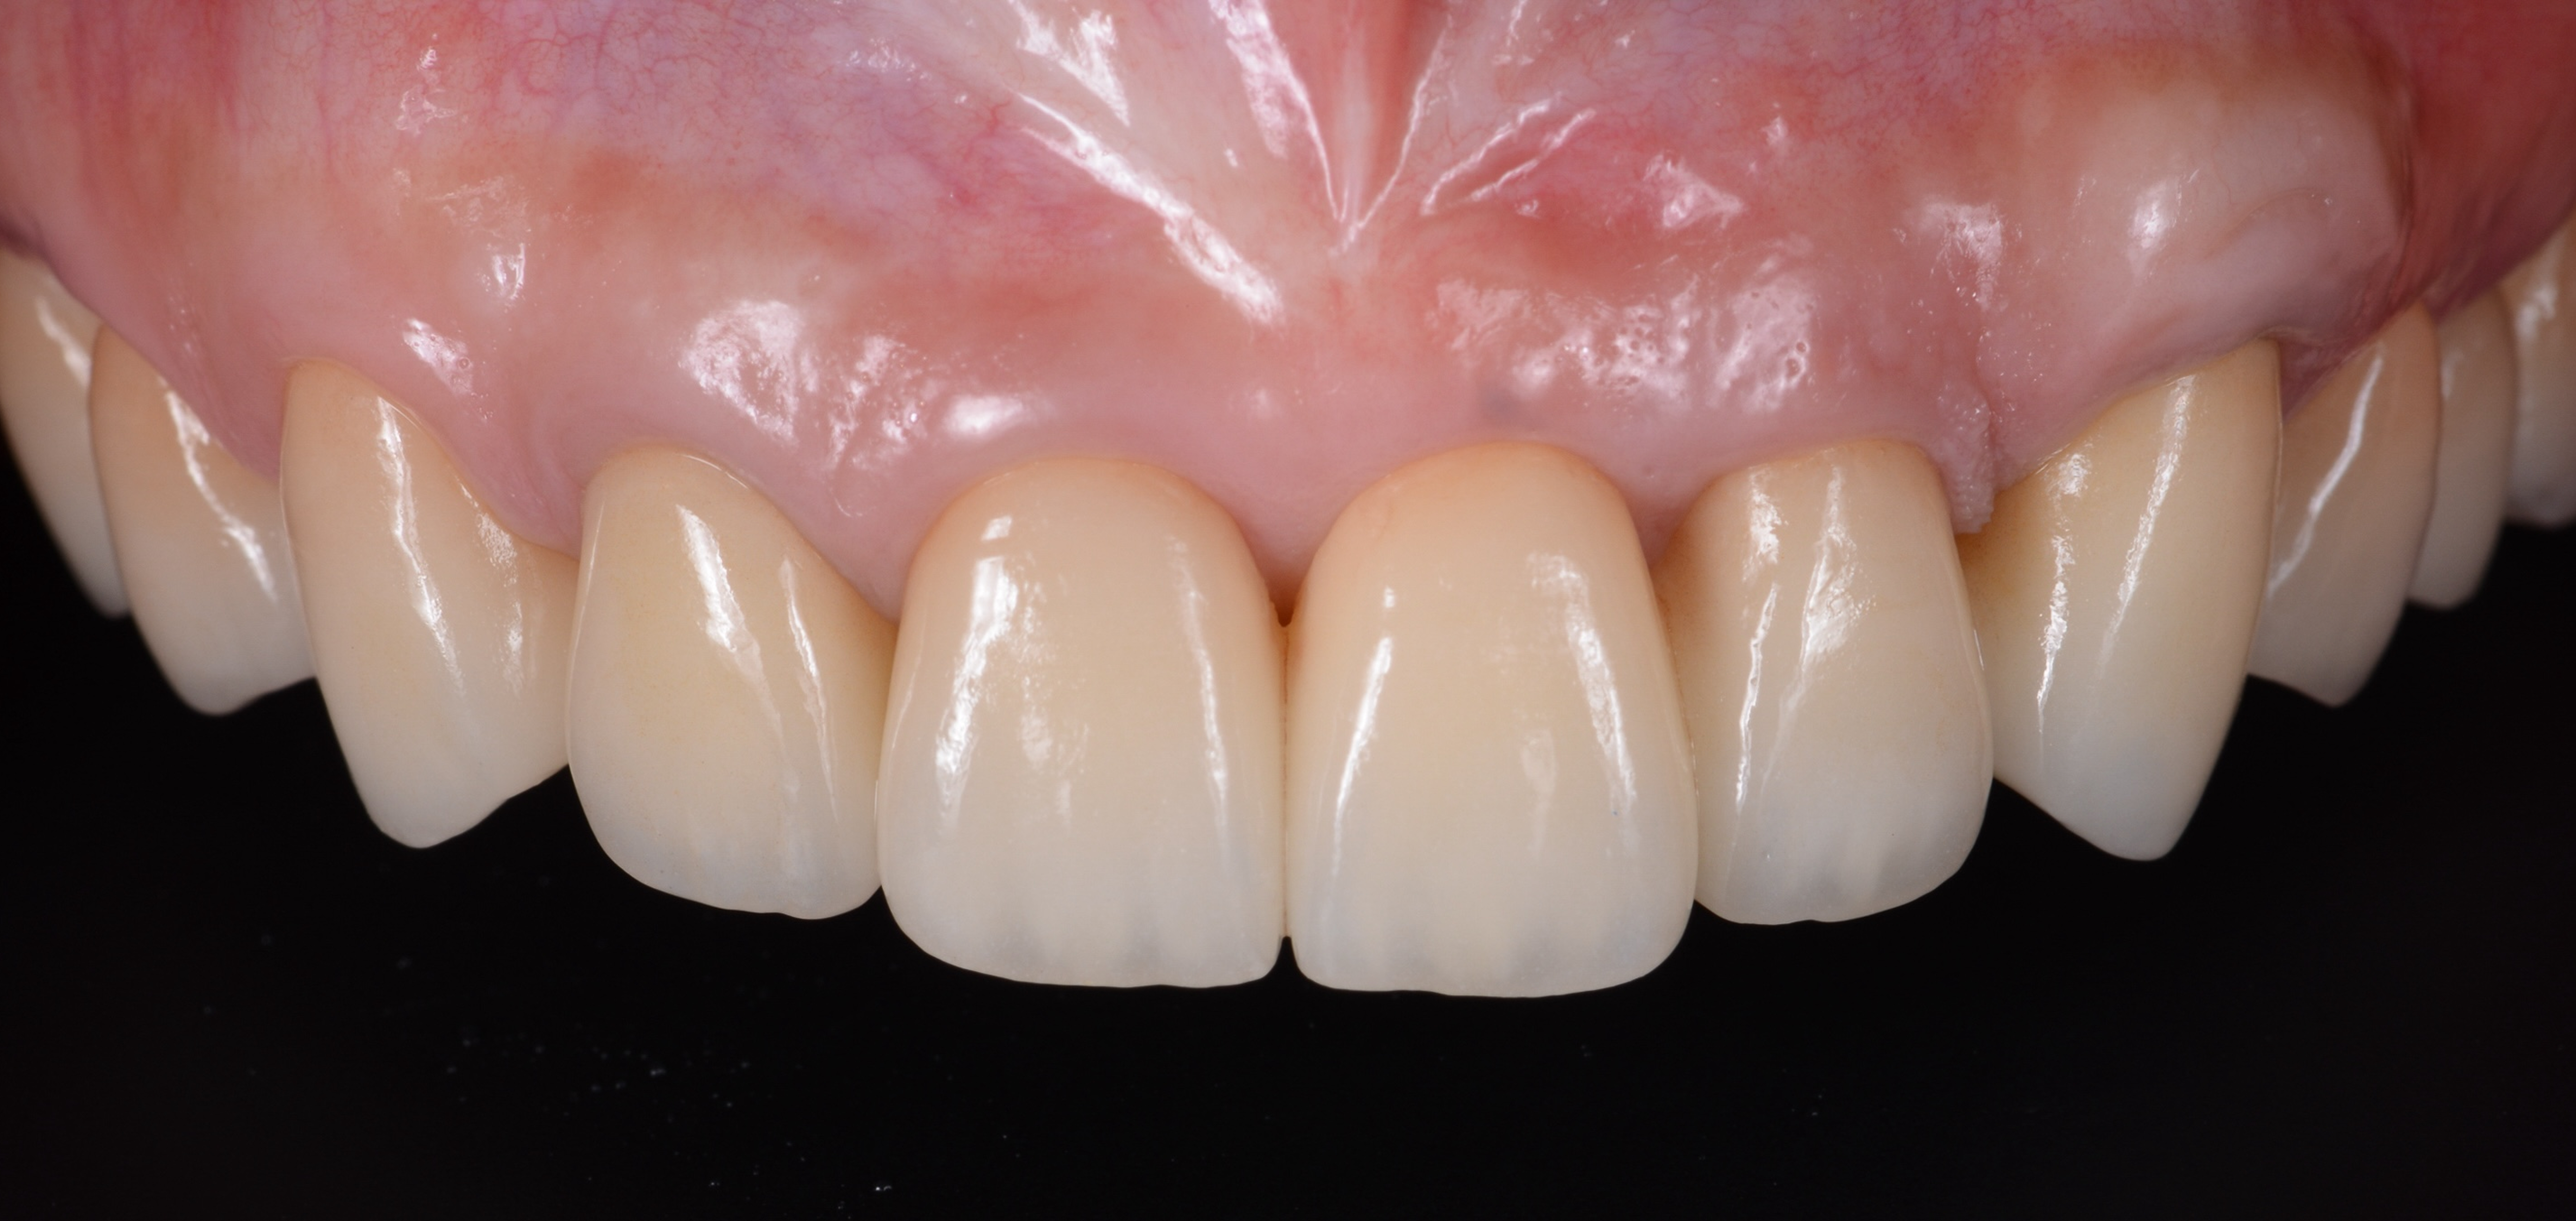

ガミースマイルを歯周形成外科で改善し、笑顔を取り戻した症例

- 年代、性別 30代・女性

- 来院動機 ガミースマイルを治したい

- 治療内容 歯周形成外科